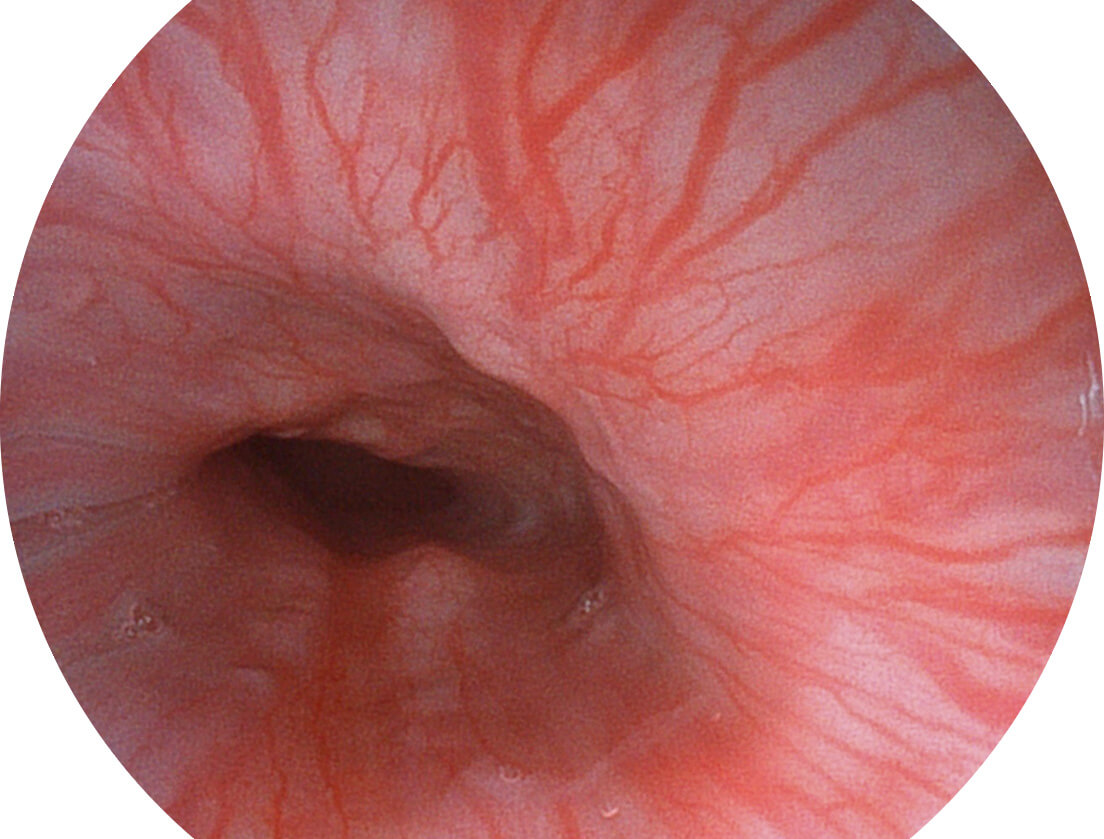

白光图像

SFI图像